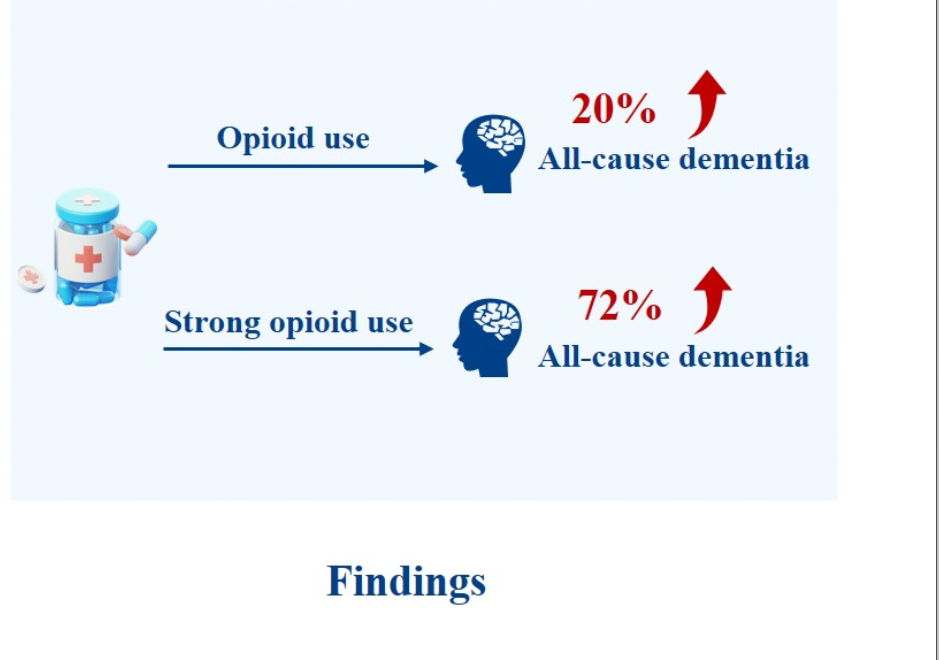

Jun 25, 2025Regular Opioid Use May Increase Dementia RiskA 20% increased risk of all-cause dementia was observed among individuals with regular opioid use compared to non-users. Chronic non-cancer pain (CNCP) is defined as any painful condition that persists for more than three months and is unrelated to malignancy, affecting around 30% of people worldwide. Opioid use for ...